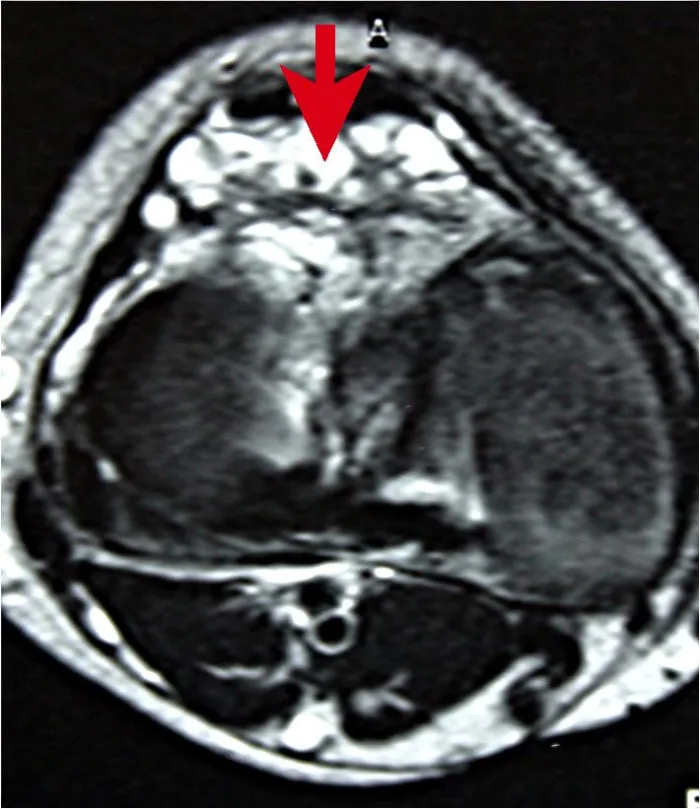

Die destruktive, angiodysplastische Arthritis unterscheidet sich wesentlich von anderen Gelenkerkrankungen. Die Zerstörung des ortsständigen Gewebes (Knorpel, Menisci, Kapsel-Bandstrukturen) tritt altersunabhängig auf. Sie kann langsam fortschreiten oder äußerst schnell mit ausgeprägter Beschwerdesymptomatik und Bewegungseinschränkung auftreten. Ätiologisch können drei pathogenetische Faktoren diskutiert werden: (1) mechanisch betrachtet, ausgelöst durch das infiltrativ-destruierende Wachstum der Gefäßfehler, in Form einer chronischen Reizung des betroffenen Gelenkes, (2) durch eine Texturstörung des betroffenen Gewebes, der Gefäße und der Gelenksubstanz (Knorpel, Knochen, Bänder und Menisci), und (3) durch mutmaßlich rezidivierende Einblutungen in das Gelenk, v.a. bei intraartikulären Gefäßinfiltrationen (Abb. 1).

Destruktive, angiodysplastische Arthritis – „Hauert Disease“ – Stadium 2 In diesem Stadium sind die klinischen Symptome, im Vergleich zum Stadium 1, ausgeprägter, die fortgeschrittene Bewegungseinschränkung ist klinisch führend. Nativradiologisch sind beginnende knöcherne Destruktionen sowie indirekte Zeichen (Gelenkspaltverschmälerung, Zystenbildung) erkennbar. Kernspintomographisch wird das Ausmaß der Beteiligung des ortsständigen Gewebes beurteilt. Therapeutisch ist ein arthroskopisches Vorgehen empfehlenswert. Bei ausgeprägter Bewegungseinschränkung (Beugedefizit über 60°) oder in Revisionsfällen kann ein offenes Vorgehen indiziert sein. Bei residuellem Streckdefizit über 20° ist eine redressierende Orthese (Quengelschiene) notwendig. Damit konnte ein gutes Ergebnis mit gering-progredienten Destruktionen bei der Nachuntersuchung festgestellt werden.

Destruktive, angiodysplastische Arthritis – „Hauert Disease“ – Stadium 3 Stadium 3 ist gekennzeichnet durch fortgeschrittene Destruktionen im Nativröntgenbild sowie durch Arthralgien mit Bewegungseinschränkung. Die Verläufe sind z. T. stark fortschreitend, so dass bereits im Kindes- und Jugendalter massiv destruktiv veränderte Gelenke zu beobachten sind. Trotz fortgeschrittener Gelenkdestruktionen konnte erstaunlicherweise allein durch ein arthroskopisches Vorgehen in 14 Fällen ein zufriedenstellendes Ergebnis erzielt werden. Weitere Therapieoption ist der endoprothetische Ersatz. Aufgrund der ausgedehnten Gefäßfehler waren modifizierte Operationstechniken in interdisziplinärer Zusammenarbeit mit dem Gefäßchirurgen notwendig. Bei ausgedehnten poplitealen Herden mit Kapselinfiltration wurde bei der Prothesenimplantation eine knöcherne Spange am dorsalen Tibiaplateau belassen, um eine Protektion gegen iatrogene Gefäßverletzungen zu haben.